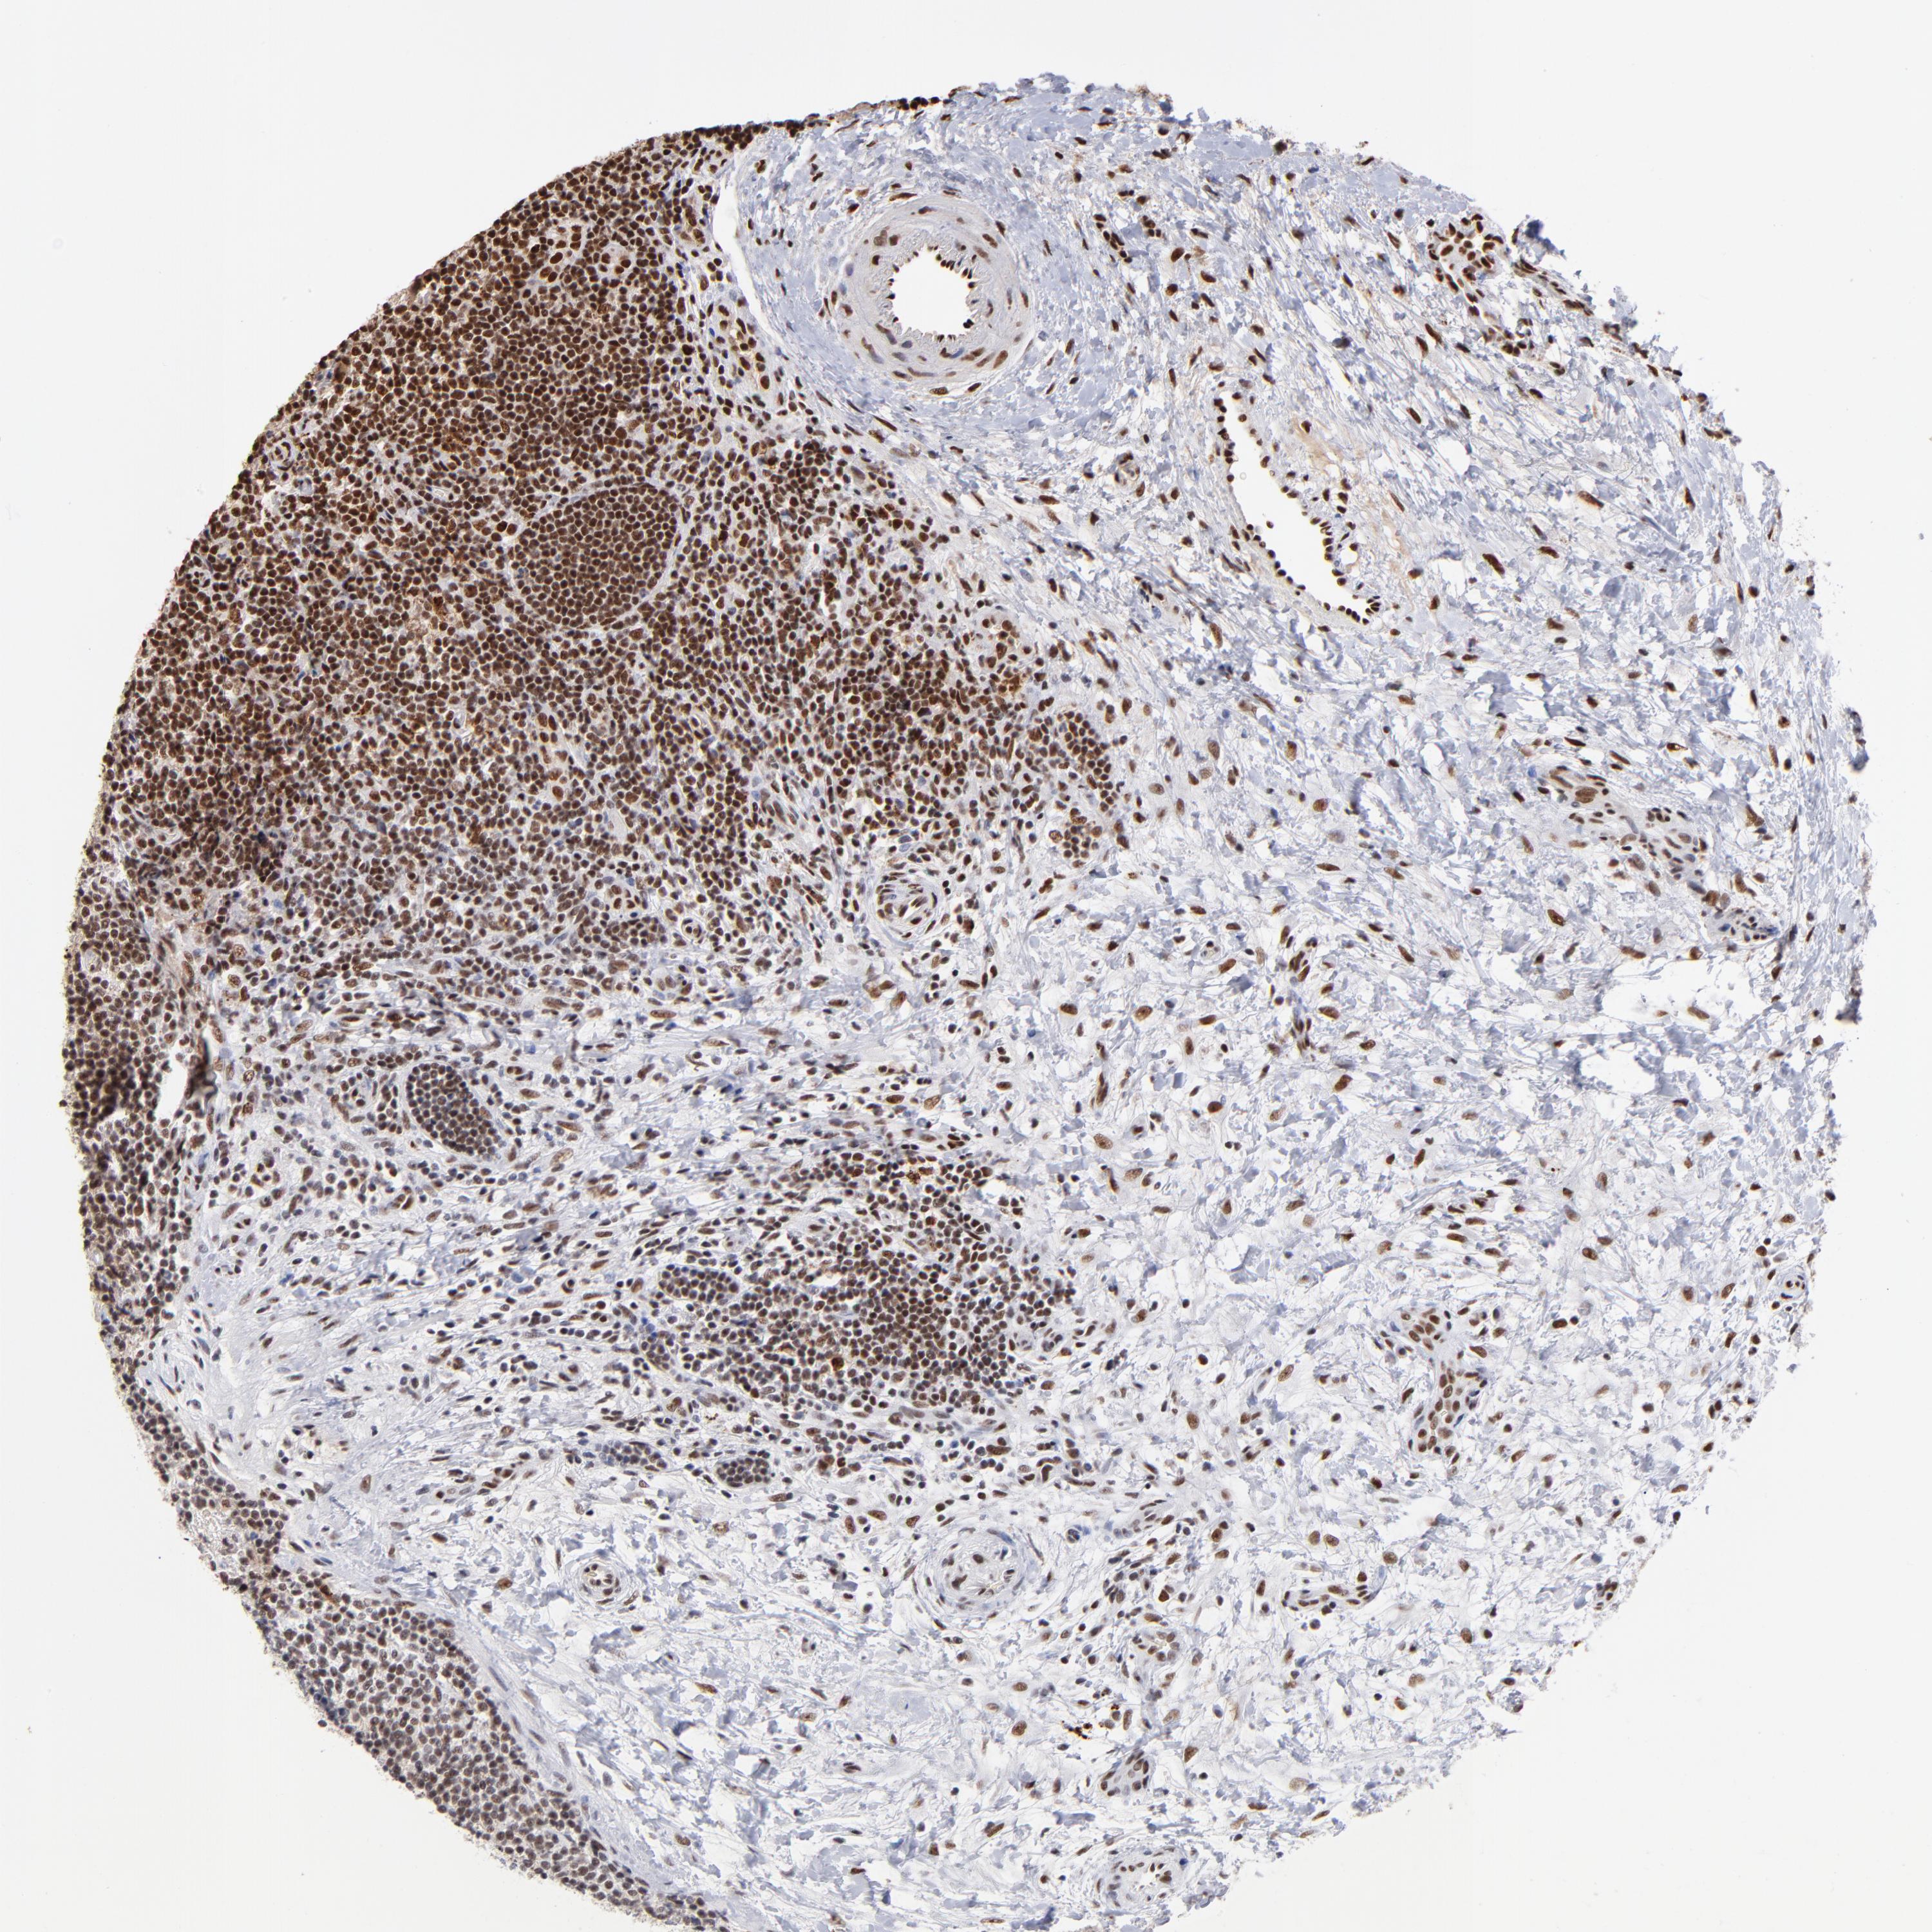

LYMPHOMA - Protein expressioni

A mouse-over function shows sample information and annotation data. Click on an image to view it in a full screen mode. Samples can be filtered based on level of antibody staining by selecting one or several of the following categories: high, medium, low and not detected. The assay and annotation is described here.

Antibody staining in the annotated cell types in the current human tissue is reported as not detected, low, medium, or high, based on conventional immunohistochemistry profiling in selected tissues. This score is based on the combination of the staining intensity and fraction of stained cells.

Each image is clickable and will lead to virtual microscopy that enables deeper exploration of all samples and also displays staining intensity scores, fraction scores and subcellular localization as well as patient and tissue information for each sample.

Antibody HPA003358

Staining

High

Intensity

Strong

Quantity

>75%

Location

Nuclear

Malignant lymphoma, non-Hodgkin's type, High grade

Malignant lymphoma, non-Hodgkin's type, Low grade

Hodgkin's disease, NOS